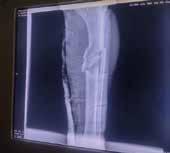

Isaac Bedollas Velázquez logró operarse en Chiclayo, pero ha tenido que endeudarse para ello.

La noche del 2 de junio, un accidente de tránsito cambió la vida de Isaac Bedollas Velázquez, de 31 años, quien sufrió la fractura de su tibia y peroné izquierdo. Desde ese momento, tuvo que sobrevivir a las de ciencias del sistema de salud. Isaac, padre y único sostén de su familia, fue atendido de emergen-

cia en el Hospital Regional II-2 JAMO, en donde luego de darle el diagnóstico, le indicaron que el vehículo responsable de su accidente no tenía SOAT y que el Seguro Integral de Salud (SIS) no cubría la operación que necesitaba en la pierna izquierda, pese a que contaba con el seguro

gratuito por estar en condición de pobreza.

Al no tener el dinero necesario para operarse, el médico le dio de alta, y gracias al apoyo de una amiga suya, logró que el hospital lo llevará hasta su vivienda, ubicada en Zarumilla, en dónde pasó varias semanas soportando el dolor y realizando distintas actividades para juntar el dinero respectivo. Nuestro medio se comunicó con el Seguro Social y la Superintendencia Nacional de Salud (SuSalud) para que puedan tomar su caso. Desde el SIS, nos informaron que el seguro sí cubría todas las operaciones y que revisarían el caso. En comunicación con Tumpis,

Bedollas comentó que el hospital JAMO lo recibió; sin embargo, no había traumatólogo. “Me dijeron que debía esperar hasta el 25 de julio”, aseguró. Los días pasaban, el dolor no paraba, y su familia, luego de conseguir una parte del dinero, lo llevó a Chiclayo el último jueves, 39 días después de su accidente, para que pueda recibir la cirugía. “Me operaron y la doctora me dijo que casi pierdo mi pierna por esperar tanto tiempo”, contó Isaac. Ahora, le esperan largos meses de recuperación. Seguirá en Chiclayo, pero tiene que devolver el dinero prestado y recibir terapia. Por ello, el 28 de julio, su familia realizará una rifa en Zarumilla. Si deseas comprar una o apoyar económicamente puedes hacer al número yape 925 771 904.